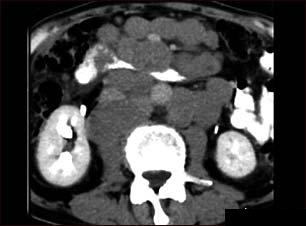

Limfoame asociate cu SIDA – Tratament